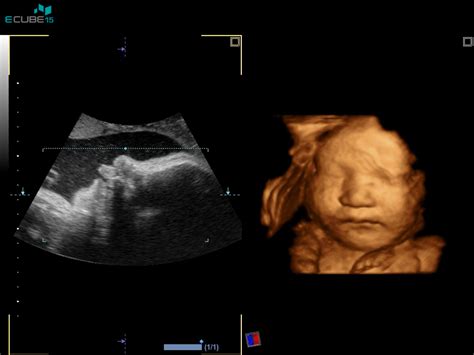

V 14. tednu nosečnosti se otrok še naprej hitro razvija. Njegova glava je še vedno nesorazmerno velika v primerjavi s preostalim telesom, vendar se njena rast zdaj nekoliko upočasnjuje. Ta sprememba omogoča, da otrokovo telo postaja čedalje bolj podobno telesu novorojenčka, kar pomeni, da se proporci uravnotežijo. Obrazne poteze otroka se še naprej razvijajo, postajajo bolj izrazite in definirane.

Ena izmed pomembnih novosti v tem tednu je možnost ugotavljanja otrokovega spola. Ginekolog vam bo morda že lahko povedal, ali pričakujete fantka ali punčko, saj se otrokovi specifični spolni organi zdaj razvijajo. Če si želite, da bi spol ostal presenečenje, je ključno, da to čim prej sporočite svojemu ginekologu pred vsakim ultrazvočnim pregledom. Pomembno je vedeti, da na tej stopnji spol iz ultrazvoka morda še ni mogoče zanesljivo ugotoviti, zato ne bodite preveč razočarani, če vam ga ginekolog še ne bo mogel razkriti.